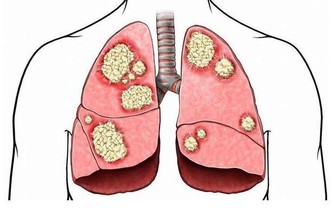

多數研究結果顯示,某些病毒感染與腫瘤的發生密切相關,如與EB病毒感染有關的鼻咽癌,與乙型肝炎病毒感染有關的原發性肝癌,以及與子宮頸癌有關的相關癌症。呼吸道、消化道、皮膚粘膜、眼睛等器官都是病毒感染的渠道。感染病毒的兒童比成人多。輕微病毒感染患者可以不需要外界干預也可以康復,嚴重感染的患者會遭受死亡威脅和殘留後遺症。